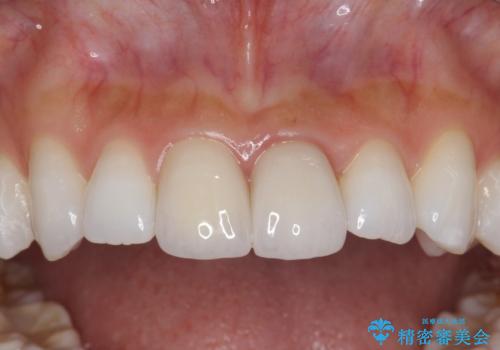

【歯周外科】審美的に気になる短い前歯の長さを歯茎の外科手術とセラミックで揃える

左上の前歯がわずかに短いことを気にされていたため、歯周外科にてこれを可及的に改善し、セラミックにて修復を行いました。

セラミックの種類:PFZ standard